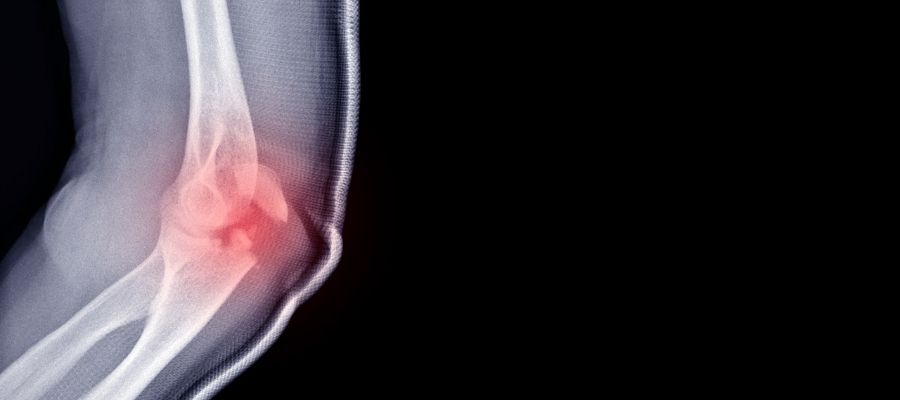

- Röntgen çekilerek kırığın yeri ve şekli görüntülenir.

Dirsek kırığının teşhisinde ilk tercih edilen yöntem röntgen görüntüleme olur ve kemikteki kırık hattı net şekilde ortaya konur. Kırığın karmaşık ya da eklem içi olduğu durumlarda, bilgisayarlı tomografi (BT) ya da manyetik rezonans (MR) gibi ileri görüntüleme teknikleri kullanılır. Bu yöntemler sayesinde hem kemik hem de çevre dokular ayrıntılı olarak değerlendirilir.